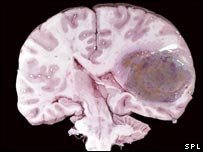

The trials, published in Cancer Cell, were carried out on 16 patients at Massachusetts General Hospital with glioblastoma brain tumours.

The patients involved in the trial all had glioblastomas which had come back despite standard treatments such as surgery, radiotherapy and chemotherapy.